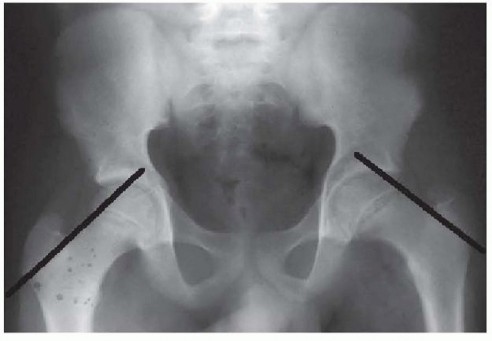

Percutaneous In Situ Cannulated Screw Fixation of the Slipped Capital Femoral Epiphysis DEFINITION Slipped ca…

Modified Dunn Procedure for Slipped Capital Femoral Epiphysis DEFINITION The modified Dunn procedure is an op…